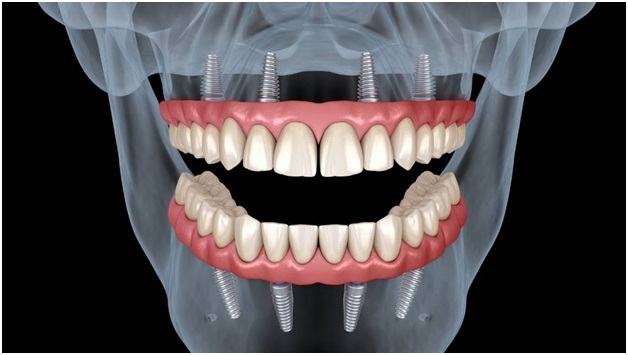

Il Protocollo All-on-4: Innovazione nel Trattamento dell’Edentulia

Una delle applicazioni più innovative della moderna implantologia è rappresentata dal protocollo All-on-4, una tecnica che permette di riabilitare un’intera arcata dentale con soli quattro impianti strategicamente posizionati.

Questo approccio sfrutta i principi biomeccanici per ottimizzare la distribuzione delle forze masticatorie, spesso evitando procedure di rigenerazione ossea complesse. La combinazione di tecnologia digitale e protocolli chirurgici avanzati rende possibile offrire ai pazienti una soluzione fissa, funzionale ed esteticamente eccellente in tempi ridotti.

I centri specializzati in implantologia All-on-4 utilizzano workflow completamente digitali, dalla diagnosi alla consegna della protesi definitiva, garantendo precisione e qualità in ogni fase del trattamento.